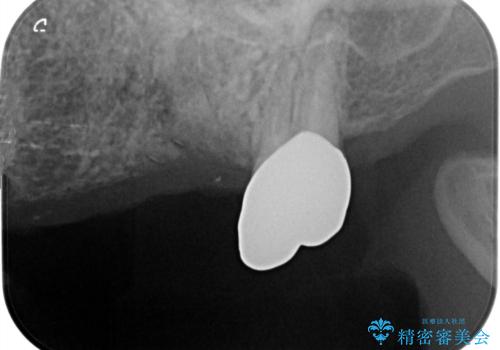

複数の奥歯の欠損 インプラントによる咬合機能回復

- 多数の奥歯を失い、咬合機能の回復を希望され来院されました。

- 105.6万円(インプラント×2・チタンカスタムアバットメント×2・ジルコニアクラウン×3・仮歯×3)費用は治療当時の料金となります